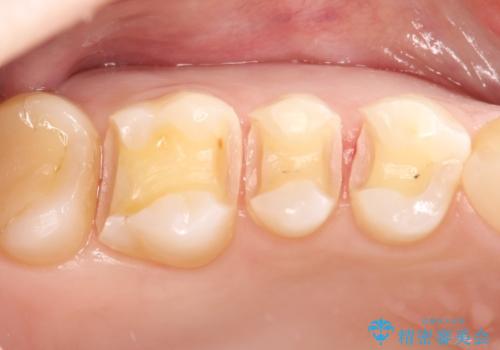

- 金属の詰め物を外して、セラミックインレーを入れたいと来院された患者様です。

奥歯に虫歯も認め、3歯の治療を来院回数2回で終了で終了しています。